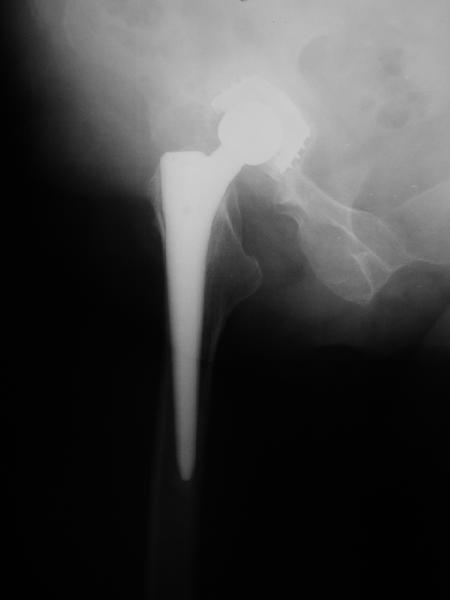

24 апреля 2005 г. левый сустав фас

24 апреля 2005 г. левый сустав профиль

Простите-не заметил последнего приложения.Не вижу рентгенологических признаков loosening.Так что изотопы могли бы и помочь

2. Судя по рентгенограммам явной нестабильности тазового ибедренного компонентов не видно, но это не решает проблемы. Гематома? - пунктируйте - не инфекция ли? Посев пунктата нужен. 3. Не спешите - погодите по времени - возможно имеет место банальная травма в области искусственного сустава с гематомой - все пройдет. Ревизия только при убеждении в нестабильности компонентов сустава или при инфекции, что пока не манифестирует. Еще раз - не спешите, не горит. С уважением и с праздником. А Рыков Хабаровка.